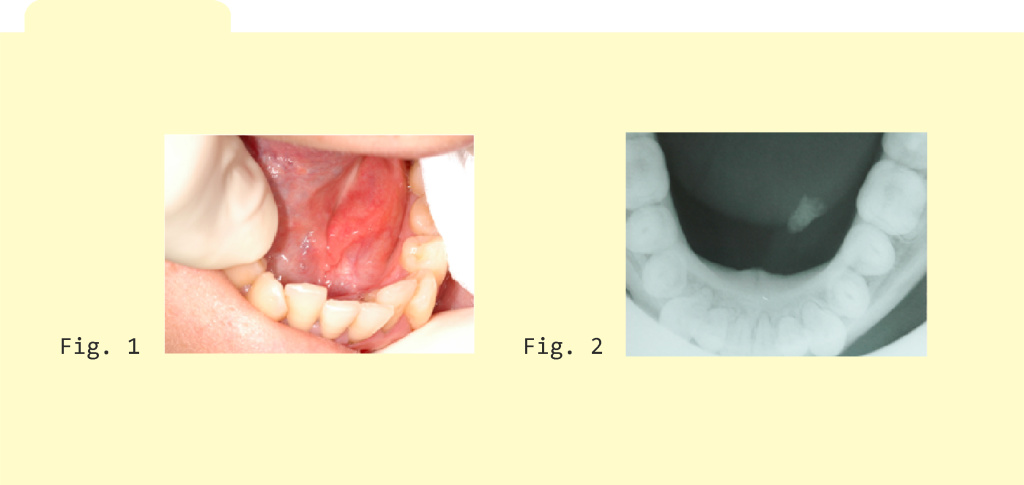

Per esemplificare riportiamo il caso emblematico di un paziente di sesso maschile, 40 anni, affetto da una scialolitiasi recidivante del dotto di Warthon sinistro (Fig. 1-2), arrivato alla nostra attenzione per le complicazioni infiammatorie ghiandolari sempre più frequenti.